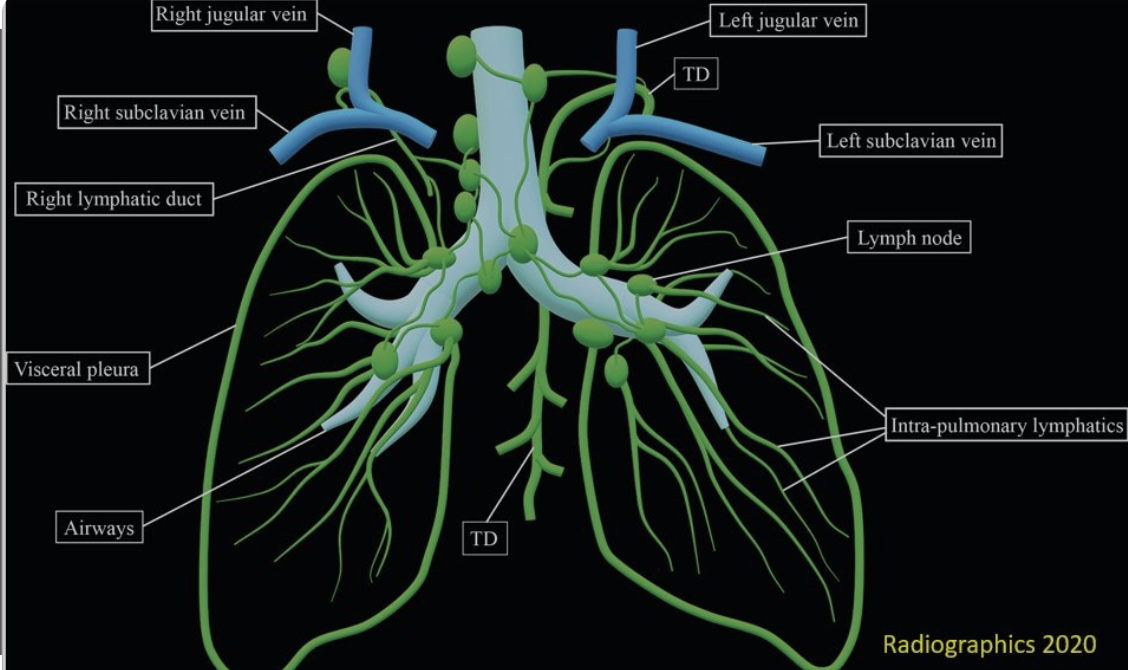

Why can pulmonary edema have an insidious onset with heart failure?

Patients with slowly progressive decompensation (eg, months in this patient) may have minimal or no pulmonary edema. This is because the pulmonary lymphatics can gradually increase fluid outflow rate up to 10 times from baseline when needed, effectively offloading fluid from the pulmonary venous system to the central venous system.